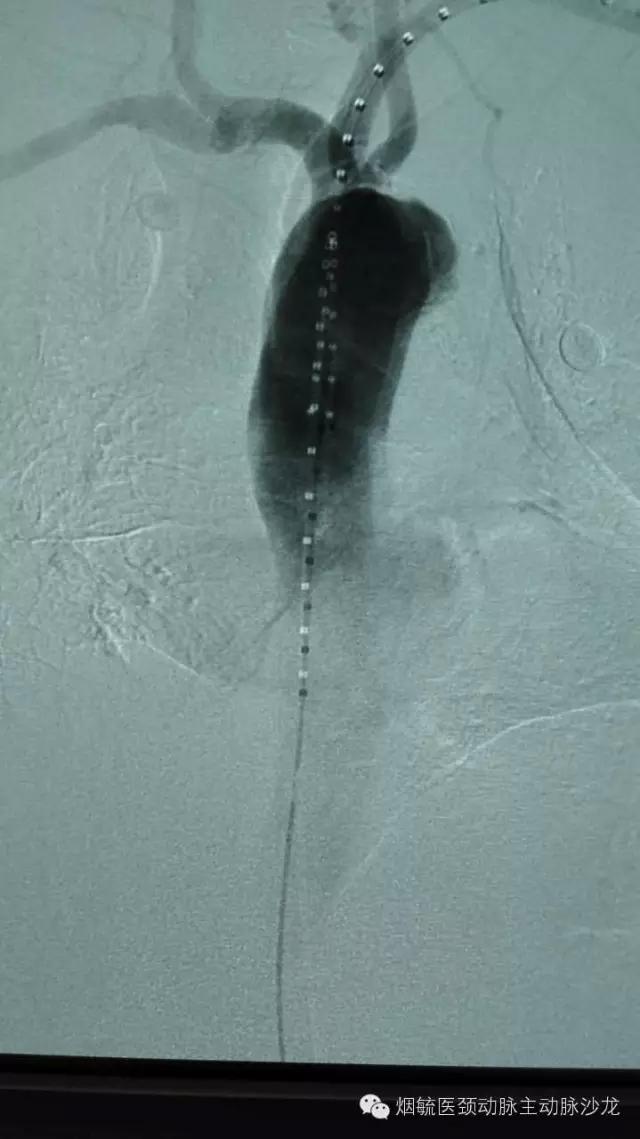

3天前60岁的王大爷前突然胸背部剧烈疼痛,疼到大汗淋漓,只能弯腰或屈膝卧床来缓解疼痛。在外院检查出胸主动脉穿透性溃疡合并璧间血肿,属于濒临破裂穿孔形成假性动脉瘤,必须立即手术,由于外院条件限制,家人带着王大爷来到烟台毓璜顶医院血管外科就诊。接诊的勇俊副主任医师为王大爷进行了紧急控制血压止痛等对症处理,并迅速组织科室行家会诊,讨论病情,制定手术方案,以杨牟教授为首的行家团队一致认为,手术刻不容缓,需紧急处理。在麻醉科及导管室工作人员的配合下,由张居文副主任医师带领的勇俊副主任医师、刘国龙主治医师和王涛住院医师构成血管外科动脉小组当天为患者实施了“胸主动脉腔内隔绝术+左锁骨下动脉烟囱置放手术”,手术顺利,患者转危为安。